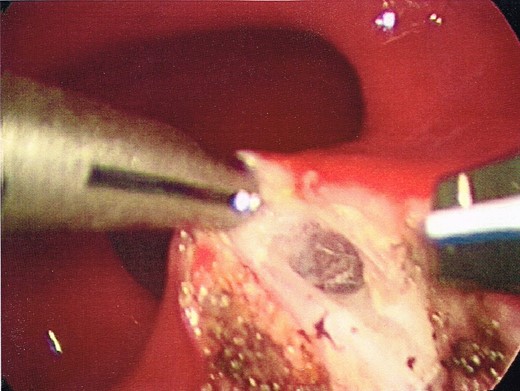

After insufflation, the contour of the retrorectal cyst could be seen distorting the posterior wall of the rectum. Using an Harmonic Scalpel (Ethicon, Johnson and Johnson), a longitudinal incision was made through the posterior midline of the rectal wall, overlying the presacral cyst (Fig. 3) in doing so, the avascular plane surrounding the cyst was able to be exposed.

Opening of the posterior wall of the rectum, into the posterior perirectal space.